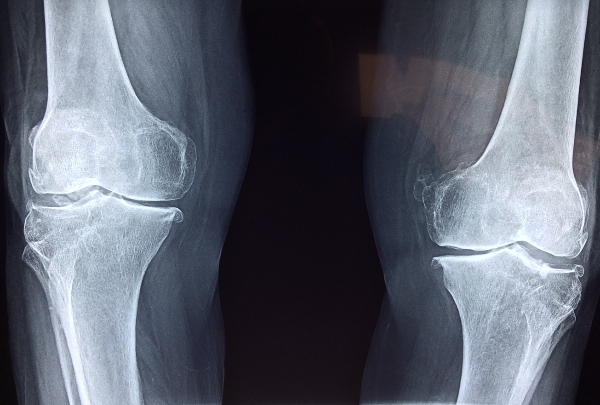

40대에 접어들면서 관절의 퇴행성 변화가 시작되면서 무릎이나 고관절 통증을 경험하는 경우가 많습니다. 콘드로이친은 이러한 관절 통증을 줄이는 데 도움을 줄 수 있습니다. 특히 관절염으로 인한 통증을 줄여주는 데 효과적이라는 연구 결과가 있습니다. 콘드로이친은 염증을 감소시키고 연골 조직을 보호하여 관절의 움직임을 개선하는 데 도움을 줍니다. - 연골 보호 및 재생 촉진

콘드로이친은 연골을 보호하고 연골 세포의 재생을 촉진하는 역할을 합니다. 40대 이후에는 연골의 손상이 점차 가속화되기 때문에, 콘드로이친이 연골의 주요 구조물인 프로테오글리칸과 콜라겐의 생성을 도와 연골 손상을 줄이는 데 기여합니다. 이로 인해 관절의 유연성을 유지하고 손상된 연골을 회복시키는 데 긍정적인 영향을 미칩니다. - 수분 유지 및 충격 흡수